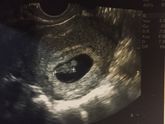

Пошла вторая половина моей Беременности???

Как же быстро время пролетело, только недавно увидела // на тесте, а сегодня мы уже такие большие! ?????

Подведём итоги первой половины:

1. Токсикоз меня не мучал ?

2. Шевелючшки начались в 15н и 4дня ???